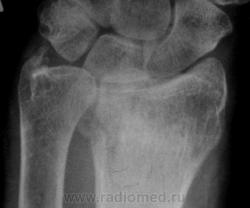

Травма. Пациент направлен на рентгенографию лучезапястного сустава.

луча в типичном месте. А вот шиловидный отросток похоже тоже сломался?